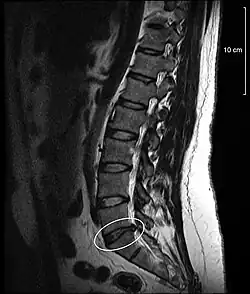

Disc protrusion

[1] A disc protrusion is a medical condition that can occur in some vertebrates, including humans, in which the outermost layers of the anulus fibrosus of the intervertebral discs of the spine are intact but bulge when one or more of the discs are under pressure.

A disc protrusion may progress to a spinal disc herniation, a condition in which there is a tear in the anulus fibrosus.[2] The most common area to have a disc protrusion is in the Lumbar Spine, specifically L-5.[2]